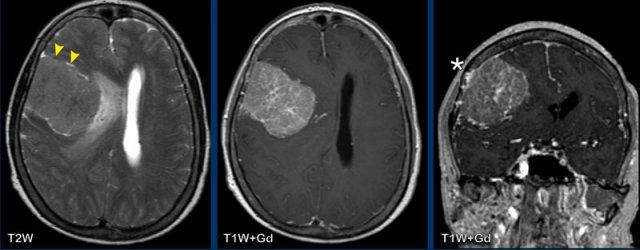

Các hình ảnh này của bệnh nhân 55 tuổi, nhập viện với các triệu chứng đau đầu và mất ngôn ngữ.

Hãy quan sát các hình ảnh trước rồi tiếp tục đọc.

Hình ảnh

Ghi nhận một tổn thương vùng trán-thái dương trái, tăng tín hiệu trên chuỗi xung T2W, với vòng viền ngấm thuốc dày và không đều.

Tổn thương lan dọc theo và xâm lấn vào chất trắng theo hướng bó móc và các sợi chữ U.

Trung tâm tổn thương không có hạn chế khuếch tán và không ngấm thuốc, nhiều khả năng là vùng hoại tử.

Chẩn đoán có khả năng nhất là GBM (u nguyên bào thần kinh đệm).

Các u thần kinh đệm có nguồn gốc từ tế bào thần kinh đệm trong hệ thần kinh trung ương và là các u xâm lấn.

GBM là u não nguyên phát ác tính nhất.

Chúng xâm lấn lan tỏa dọc theo các bó chất trắng, ví dụ như thể chai.